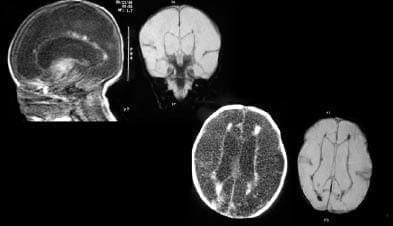

Foto 1. Caso hidranencefalia

reportar casos nuevos e investigar sobre el pronóstico, tratamiento y evolución de los pacientes con hidranencefalia (Foto 1).

Foto 3. Tomografía.

Foto 4. Tomografía.

La TAC cerebral (Fotos 3, 4 y 5), muestra alteración difusa en la densidad de la corteza y la sustancia blanca en relación con degeneración quística vista en pacientes con hidranencefalia severa, se conserva la densidad de los territorios de la circulación posterior; se toma resonancia magnética cerebral (Foto 9), siendo los hallazgos compatibles con hidranencefalia, sin signos de hipertensión endocraneana. Por el estado clínico del paciente se considera continuar seguimiento ambulatorio por neuropediatría, neonatología y pediatría.